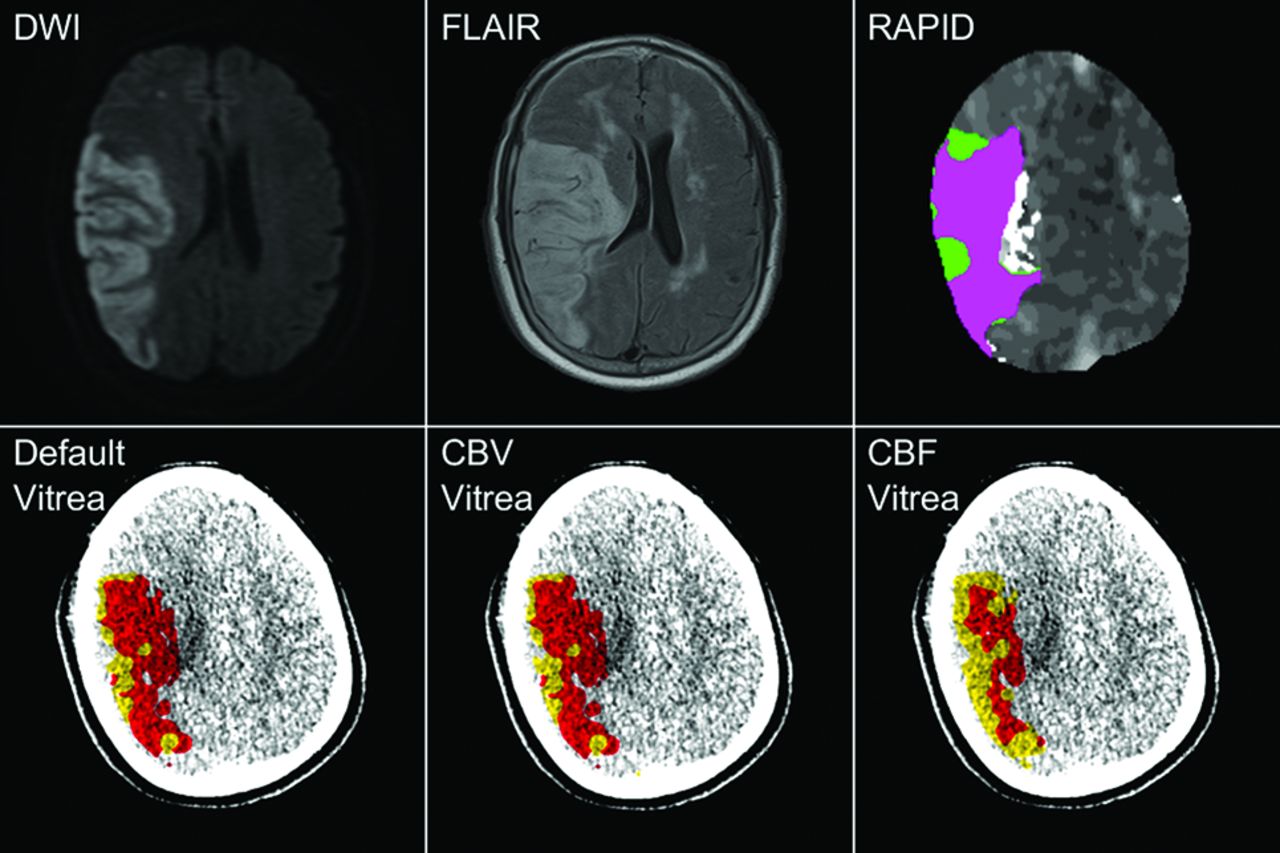

RAPID analysis was conducted offsite by sending CTP volumes from the CT scanner to iSchemaView and receiving predicted ischemic volumes through the PACS of the hospital. With RAPID, infarct is tissue with CBF <30% compared with the contralateral hemisphere and penumbra is volume of tissue with a Tmax of >6 seconds. Fig 1 compares all 3 Vitrea settings and RAPID with DWI and FLAIR in predicting FIVs for the same patient without an intervention.

Ground truth infarct labels with the hyperintensified regions in the DWI and FLAIR identifying infarct. Default, CBV, and CBF Vitrea perfusion analysis demonstrates infarct as red and penumbra as yellow, while RAPID perfusion analysis represents infarct as pink and penumbra as green. For this nonintervention case, there is agreement between Vitrea and RAPID infarct volumes and their respective locations within the MR imaging scans. Final infarct volumes for each MR imaging method and CTP software (summation of infarct and penumbra due to it being a nonintervention case) are as follows: DWI = 135.0 mL, FLAIR = 167.6 mL, default Vitrea = 132.4 mL, CBV Vitrea = 141.2 mL, CBF Vitrea = 115.3 mL, RAPID = 176.0 mL.